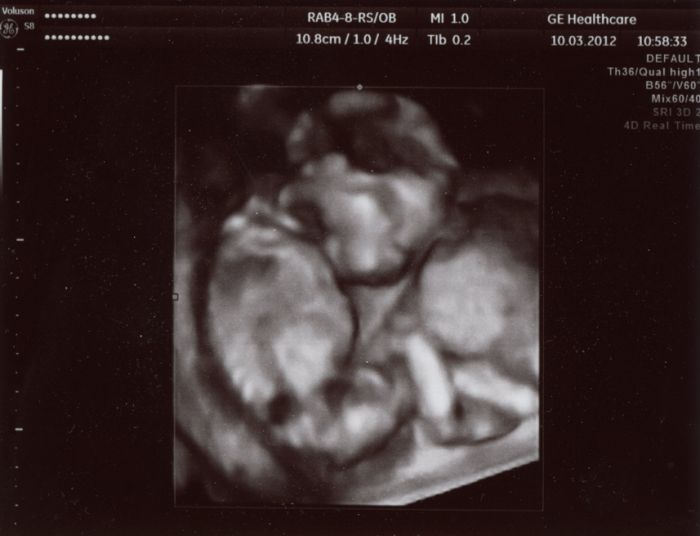

Ahoj holky :-) Až teď píšu, protože jsem po UZ hned jeli pryč na víkend. Takže hlásím, že je vše v pořádku. Miminko má od hlavičky po zadeček 15cm, mrskalo se tam a pořád se šťouralo v oušku nebo v očích. Dr. si nejdřív myslel, že je to kluk, ale pak znejistěl, neboť tam nic neviděl, nebo spíš to nebylo úplně jasně vidět. Každopádně jasnej pindík tam sice vidět nebyl, ale nechtěl nám s jistotou potrvzovat holčičku, co kdyby tam dole ještě něco narostlo??!! ;-) Takže opět nevím nic, ale my se přikláníme k tomu, že to bude holčička ;-)

Tady je pár foteček. Video dostanu za 2 týdny až tam půjdu na kontrolu. Ten jeho přístroj mu to nedovede hned zpracovat, tak nám to video nemohl hned dát.

Tedy Blanko, to jsou fakt nááádherné fotečky!

Fakt krásně vyfocené....Tak to moc gratuluji!

Člověče,nevím proč, ale také mi to miminko přijde jako holčička